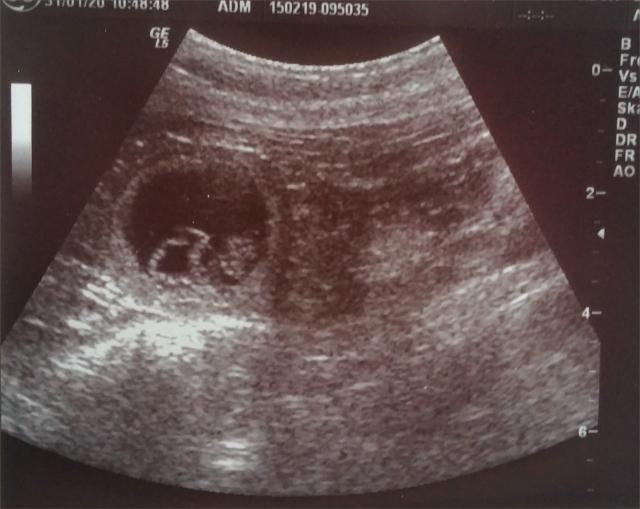

31.01.2020: Wir waren heute beim Ultraschall mit Gina

und haben kleine Babys im Bauch gesehen! :-)

Somit erwarten wir unseren A2-Wurf Anfang März! Bei

Interesse bitte melden! :-)